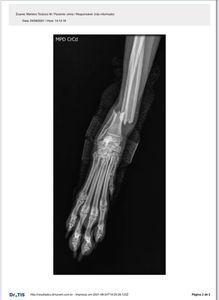

Me chamo Olívia. Sou muito sapeca e enquanto brincava atrás da minha bolinha eu quebrei minha patinha 🐾🥺

Mamãe me levou correndo pro vet, fizemos um raio-x e a coisa tava feia! Vou ter que operar, acreditam? Logo agora que eu tava planejando ir pra creche tomar banho de mangueira pra espantar esse calor.